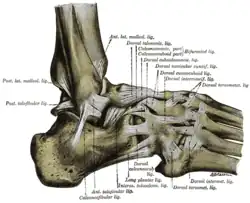

![]() Фронтальный распил голеностопного сустава и суставов стопы. | |

Большеберцовая и малоберцовая кости охватывают блок таранной кости наподобие вилки. Суставная капсула сзади и по бокам прикрепляется к краям сочленяющихся поверхностей, а спереди на полсантиметра отступает от них. Связки располагаются на боковых поверхностях сустава[3]:

- На внешней стороне сустава расположены передняя и задняя таранно-малоберцовые и пяточно-малоберцовая связки — все они расходятся веерообразно, начинаясь на латеральной лодыжке: передняя таранно-малоберцовая связка (лат. ligaméntum talofibuláre antérius) крепится к шейке таранной кости, задняя таранно-малоберцовая связка (лат. ligaméntum talofibuláre postérius) — к заднему отростку таранной кости, а пяточно-малоберцовая связка (лат. ligaméntum calcaneofibuláre) спускается вниз, оканчиваясь на наружной поверхности пяточной кости.

- На внутренней стороне голеностопного сустава расположена дельтовидная (медиальная) связка (лат. ligaméntum deltoídeum seu mediále), которая начинается на внутренней (медиальной) лодыжке и делится на четыре части:

- большеберцово-ладьевидная часть (лат. pars tíbionaviculáre) прикрепляется к ладьевидной кости стопы;

- большеберцово-пяточная (лат. pars tíbiocalcánea) крепится к пяточной кости;

- передняя и задняя большеберцово-таранные части (лат. pártes tíbiotaláres antérior et postérior), прикрепляющиеся к таранной кости.